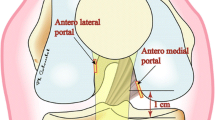

For the creation of femoral tunnels, the 3D image of lateral half of femoral condyle was reconstructed on a monitor for better view of lateral wall and roof of the femoral intercondylar notch. A transtibial or accessory anterior medial portal technique was used for the creation of femoral tunnel, and the target was set on the center of the anatomic footprint of each bundle in reference to intercondylar ridge and bifurcate ridge if it was identified (Fig. 2c). The 2 intra-articular outlets of the femoral tunnels did not overlap on the lateral femoral condyle in any of the knees encountered.

To create the femoral tunnel, a 3D lateral image of distal femur sagittal view was shown on the navigation computer monitor. The femoral footprints of the AM bundle were marked using the navigation awl with the assistance of the computer monitor images projected during preoperative planning. Transtibial drilling through each tibial tunnel was our first option. However, if the femoral marking holes were hard to reach using the transtibial approach, we created femoral tunnels through the accessory anteromedial portal. When we selected the anterior medial portal approach, simulation was done before inserting the guide wire. On the navigation computer screen, the 3D image of the distal femur was rotated to face the posterolateral aspect of the femur. The virtual femoral tunnel diameter was set to the real diameter of the AM graft. The navigation pointer tip was placed at a small hole on the AM footprint, and knee was flexed 90 to 120–130 degrees. When flexing the knee, risk of the posterior wall breakage and sufficiency of the bone tunnel length were evaluated (Fig. 4).

As the second advantage, CT-based navigation is applicable to various surgical techniques and can provide useful information on each procedure during the surgery. The transtibial method for femoral tunnel preparation is limited to reach the anatomic femoral footprint, because with a narrower tibial tunnel diameter compared to the single-bundle procedure, the influence by tunnel direction or outlet on tibial condyle becomes greater. In our procedure, this kind of mismatch could be reduced by preoperative planning of direction of tibial bone tunnel and outlet on tibial condyle and by strict control during the surgery. However, several recent studies have shown that transtibial approach can limit the ability to place the femoral tunnel anatomically, even if tibial tunnels are placed in accurate positions [8]. For this reason, the AM portal procedure has been increasingly reported recently. On the other hand, in this procedure, risk of cartilage injury and posterior wall breakage of lateral femoral condyle had been reported [15]. In the presently reported navigation system, pertinent information could be obtained using a navigation pointer before actual guide wire insertion, including insertion direction, confirmation of whether injury to cartilage or posterior wall breakage had been avoided, or whether sufficient length of bone tunnel was secured.